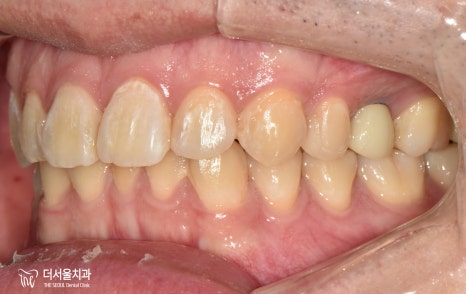

측면을 봤을 때도 성남 치아교정을 하고 나서

치열이 좋아진 것을 볼 수 있습니다.

게다가 임플란트 식립까지 잘 되었구요.